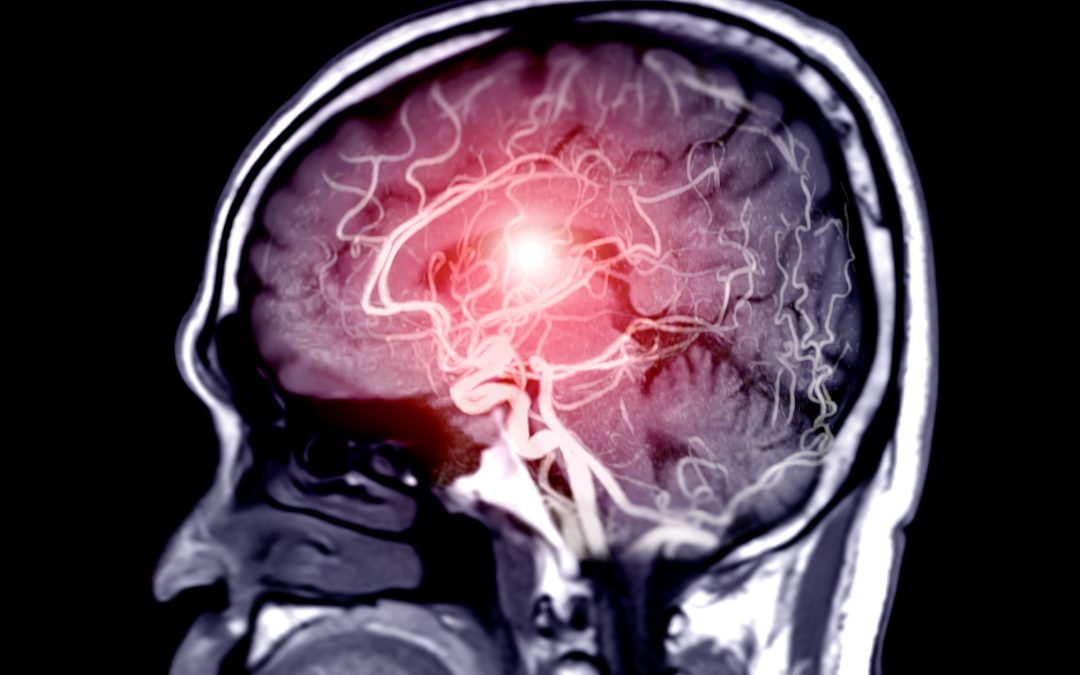

- Las arterias cerebrales, donde puede desencadenar un accidente cerebrovascular hemorrágico.

- Visión doble o dolor intenso de cabeza en caso de aneurismas cerebrales

🔹 Angiografía por TAC o resonancia magnética

Se utiliza cuando se requiere una visualización precisa del flujo sanguíneo y del entorno vascular. Son herramientas clave para casos complejos o decisiones quirúrgicas.